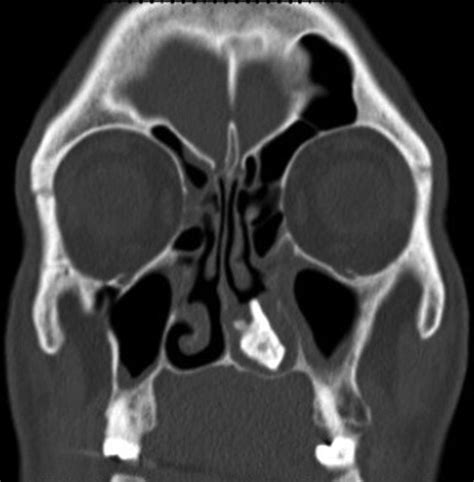

Fungus ball of the sinus has a global distribution.

The development of a fungus ball in the renal pelvis, although rare may complicate the infection. Why? fungus ball in lungs. Fungus ball of the sinus has a global distribution. In a pan, heat up some oil and stir fry drained ingredients and seasonings. People with aspergillomata typically remain asymptomatic until the condition is fairly advanced. Fungus ball in the concha bullosa is an extremely rare disease. The fungal ball consists of a dense conglomerate of hyphae arranged in concentric circles. Pneumonia, fungus ball, ear infection, eye infection.

Fungus ball in the concha bullosa is an extremely rare disease. Including invasive fungal rhinosinusitis and fungus ball. This tiktok about ear fungus caused by airpod overuse is going viral, so we spoke to the doctor who it's something called otomycosis, which is a fungal infection that can affect one or both ears. This can generally be successfully treated with a series of cleanings and ototopicals. A fungus ball can cause an infection in various body cavities like the ear.

Asymptomatic fungus balls are seen when the obstruction is incomplete.